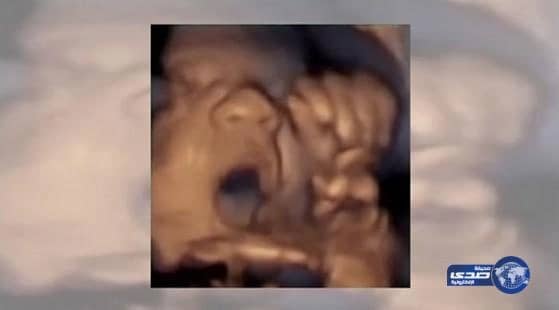

بالفيديو.. طفل "يغني" وهو في بطن أمه

كشفت دراسة حديثة أن الجنين بعمر 16 أسبوعاً يصبح قادراً على السمع، وهو في بطن أمه.

وأظهر فيديو بالأمواج فوق الصوتية جنيناً يتفاعل مع الموسيقى بتحريك فمه ولسانه فيما يبدو أنه يغني معها، وفق ما نشر "ديلي ميل".

وتكون أذنا الجنين مكتملتي النمو عندما يكون قد بلغ أربعة أشهر (16 أسبوعاً).

لكن المختصين حتى الآن لا يعتقدون أن الطفل يكون قادراً على السماع حتى 18 أسبوعاً، بينما الشائع أنه يتمكن من ذلك في عمر 6.5 شهر.